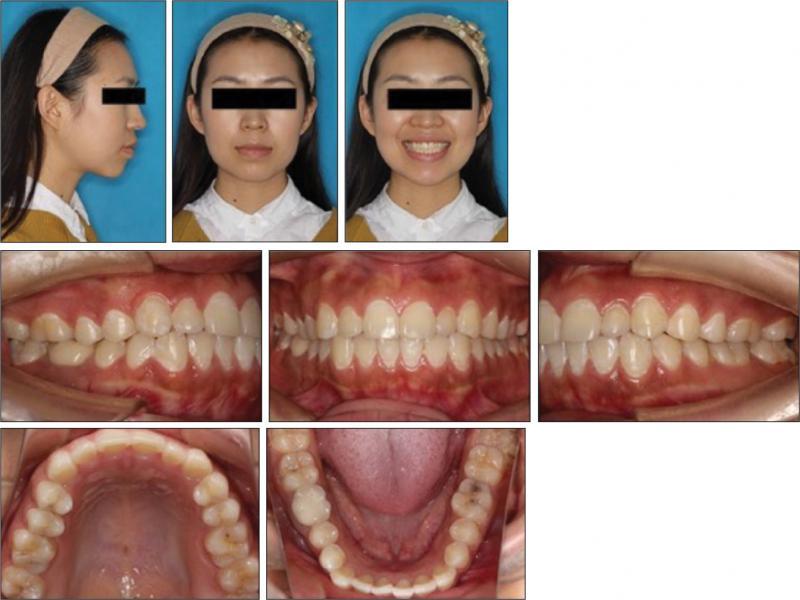

A 22-year-old female presented with the main complaint of “protrusive lips” and said she “would like to have treatment with clear aligners” because of her work as an actress. A facial analysis showed that there was a symmetrical face, a convex profile and a decreased nasolabial angle (Figure 1). No temporomandibular joint disorder was noted during the consultation and clinical examination. An intraoral assessment revealed that there was an Angle Class I molar relationship on her left side and a Class III relationship on the right side, a 1 mm overjet and overbite, and symmetrical dental arches with no crowding. Both upper and lower midlines were 1 mm to the left of the facial midline. No mandibular functional shift was observed (Figures 1 and 2).

Pretreatment facial and intraoral photographs.

Pretreatment dental casts.